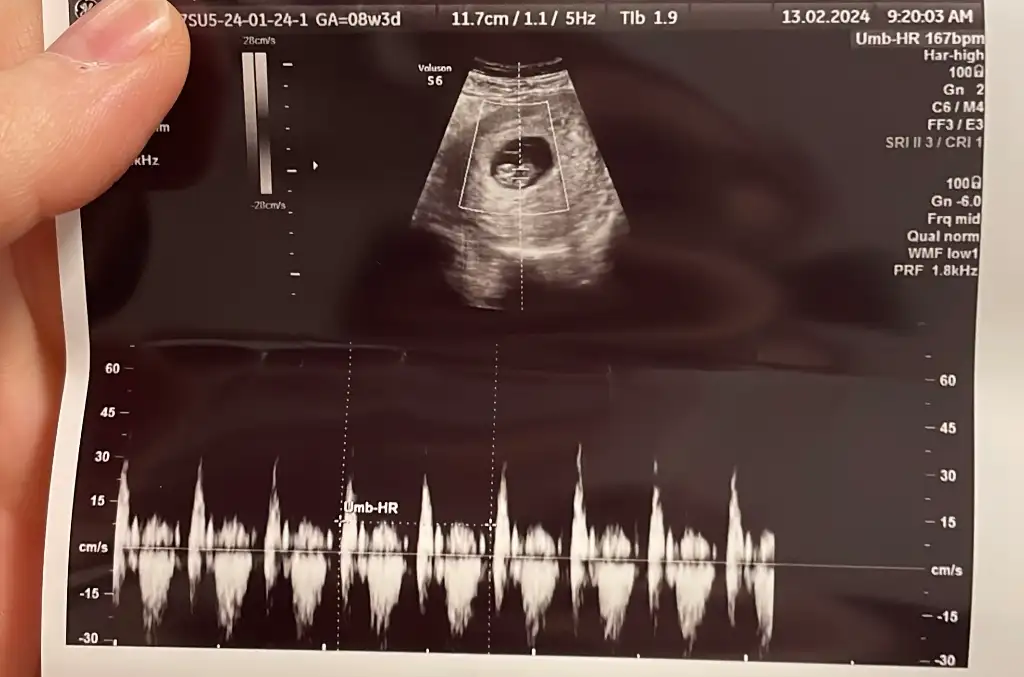

• 30E789FB-6988-43AF-ADE7-4C5BD9A0D129.webp

30E789FB-6988-43AF-ADE7-4C5BD9A0D129.webp

32,6 KB · Görüntüleme: 41